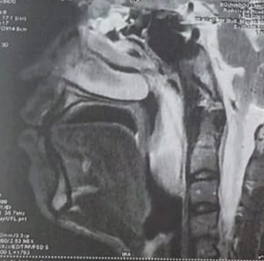

were clear (Figure 2). MRI of the

face revealed an oblong mass filling the lumen of the cavum originating in the

right nasal cavity opposite the middle meat and extending into the oropharynx (Figure 3). At surgery, the

Figure 3. Coronal and

sagittal sections of a facial MRI: Insertion site of the mass in the middle

turbinate and extension into the nasopharynx (a) and oropharynx (b).